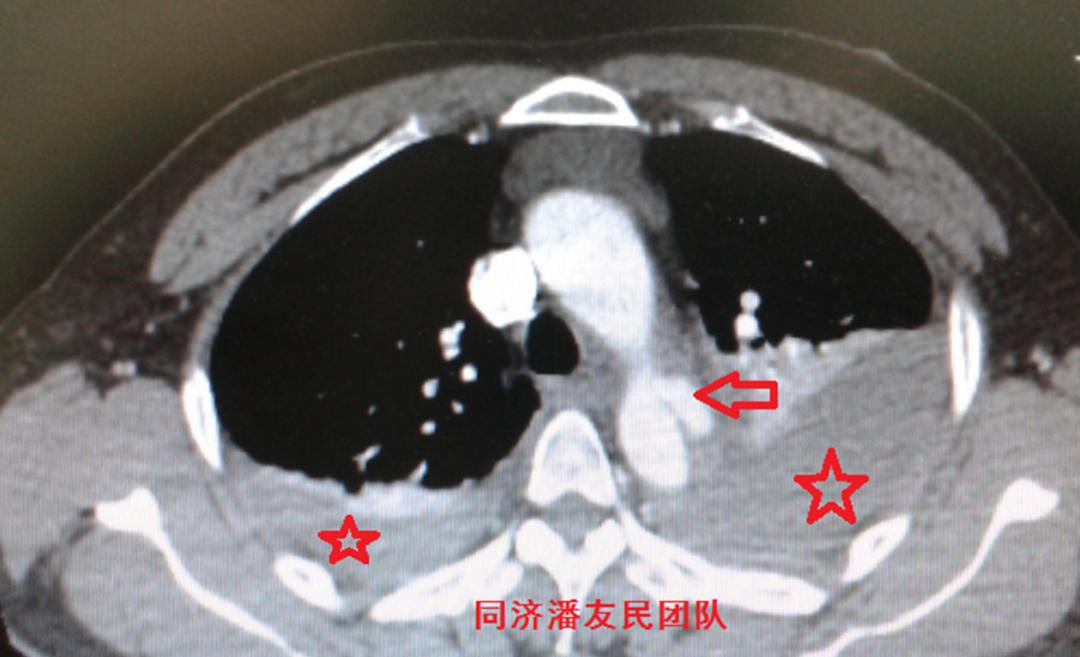

基层医院平扫CT提示胸降主动脉起始部内膜片影(图1),疑诊主动脉夹层(如何从平时CT发现主动脉夹层,请参考下文链接:没有CTA?这三招也能识别主动脉夹层!)。

红星号显示纵隔血肿,白箭头显示胸腔积液。